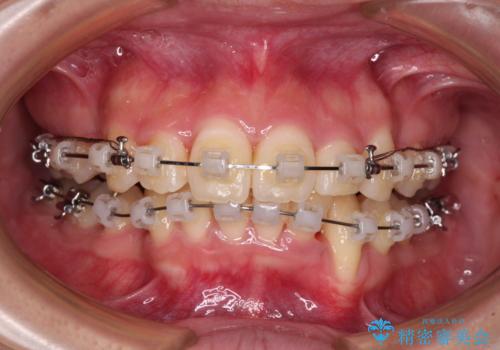

- クリアブラケット

- 3年4ヶ月

- 30回以上

どこまで口元の突出感を改善できるのか不安でしたが、舌のトレーニングをしっかりと行ってくださり、我々も驚くほど劇的に改善することができました。